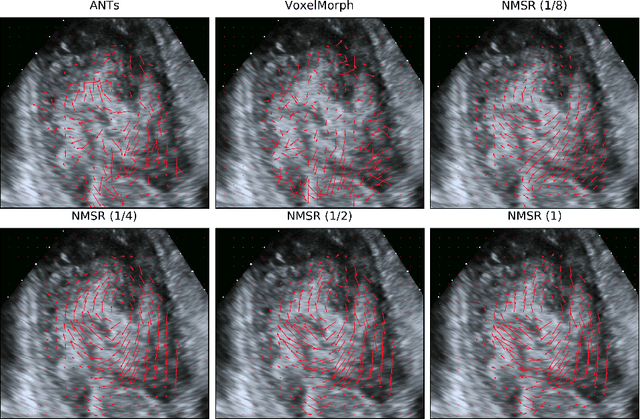

Abstract:Echocardiography has become routinely used in the diagnosis of cardiomyopathy and abnormal cardiac blood flow. However, manually measuring myocardial motion and cardiac blood flow from echocardiogram is time-consuming and error-prone. Computer algorithms that can automatically track and quantify myocardial motion and cardiac blood flow are highly sought after, but have not been very successful due to noise and high variability of echocardiography. In this work, we propose a neural multi-scale self-supervised registration (NMSR) method for automated myocardial and cardiac blood flow dense tracking. NMSR incorporates two novel components: 1) utilizing a deep neural net to parameterize the velocity field between two image frames, and 2) optimizing the parameters of the neural net in a sequential multi-scale fashion to account for large variations within the velocity field. Experiments demonstrate that NMSR yields significantly better registration accuracy than state-of-the-art methods, such as advanced normalization tools (ANTs) and VoxelMorph, for both myocardial and cardiac blood flow dense tracking. Our approach promises to provide a fully automated method for fast and accurate analyses of echocardiograms.